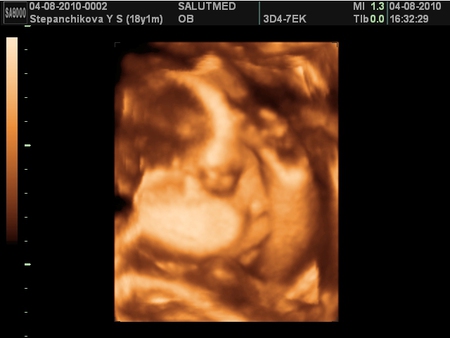

Пупс)

Ходили на 3D УЗИ) в восторге) узи по идеи последнее) дальше только личная встреча с малышом)) Вот подробный отчет:

ну вот и фотки малыша для полного заключения)